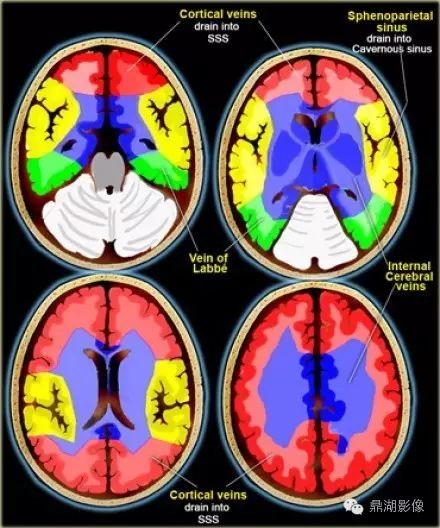

红色ACA:大脑前动脉

黄色MCA:大脑中动脉

绿色PCA:大脑后动脉

蓝色PICA:小脑后下动脉

紫色AICA:小脑前下动脉

灰色SCA:小脑上动脉

浅蓝Branches from Vertebral arteries:椎动脉分支

墨绿Branches from Basilar artery:基底动脉分支

天蓝ACHA:脉络膜前动脉

橙色LSA:豆纹动脉

SSS:上矢状窦

Vein of Labbe:labbe静脉-汇入横窦

Inernal cerebral veins:大脑内静脉-汇入Galen静脉

Sphenoparietal sinus:蝶顶窦-汇入海绵窦